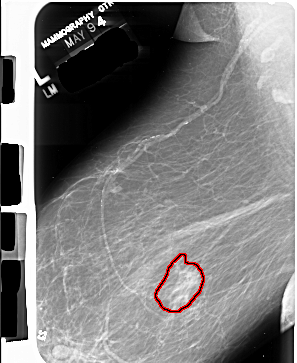

A_1014_1.LEFT_MLO

LEFT_MLO LINES 6886 PIXELS_PER_LINE 5641 BITS_PER_PIXEL 16 RESOLUTION 42 OVERLAY

FILE: A_1014_1.LEFT_MLO.OVERLAY

TOTAL_ABNORMALITIES 1

ABNORMALITY 1

LESION_TYPE MASS SHAPE IRREGULAR MARGINS ILL_DEFINED

ASSESSMENT 4

SUBTLETY 4

PATHOLOGY MALIGNANT

TOTAL_OUTLINES 1

BOUNDARY